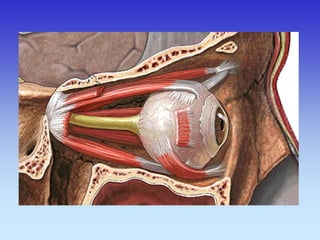

ORBITE